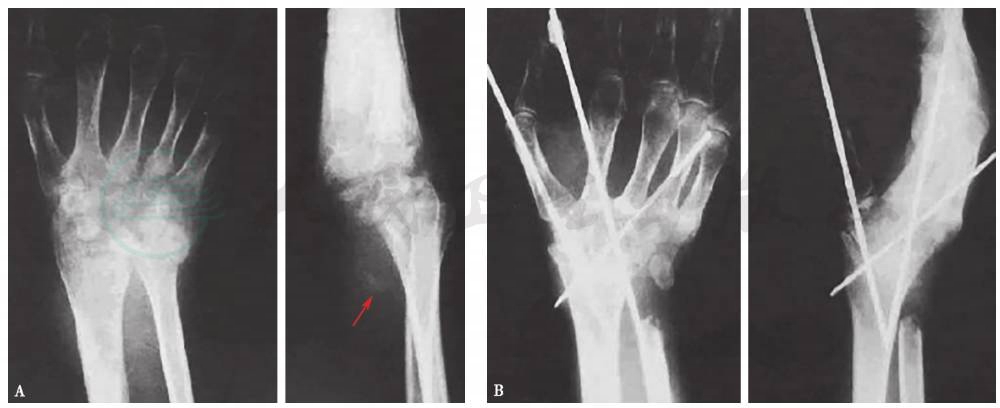

图1腕关节结核融合术前(A)、后(B)X线片

病灶彻底清除干净后,于桡骨下端开一个长约3cm的骨槽,将所取髂骨修整后上端嵌入桡骨下端骨槽内,下端插入第3掌骨基底骨髓腔内。术毕外加前臂腕掌石膏托固定腕关节于背伸30°功能位,植骨欠稳定者可用克氏针穿过桡骨下端及腕掌骨加固,3个月后摄片示植骨融合后,拆石膏练习活动。

对于病变已静止的腕关节骨性或纤维强直呈有明显手下垂及尺偏畸形者可将桡骨下端作楔形切除矫正尺偏,并用交叉克氏针固定,同时将尺骨头切除,术毕石膏托外固定6周。单纯前臂旋转障碍者可仅作尺骨头切除即可,无须外固定。

图13-35腕关节结核融合术前(A)、后(B)X线片